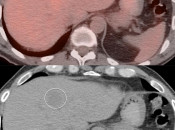

Assessment of a potential malignant lesion within most solid organs involves comparing the metabolic activity of the lesion to the background uptake within that organ (e.g. if a potential liver lesion’s metabolic activity is greater than the background activity of the liver, then the lesion is highly suspicious for malignancy).

There are a few exceptions to this rule, which are addressed in the The Cancers section. For example, many adrenal lesions are assessed by comparing their activity to the liver, not to the adrenal gland itself.

Pulmonary Nodules:

Assessment of a pulmonary nodule involves comparison of its metabolic activity to either background lung uptake (meaning that any uptake in a lung nodule is worrisome) or to mediastinal blood pool uptake.  Assessment of pulmonary nodules is addressed in detail, here.